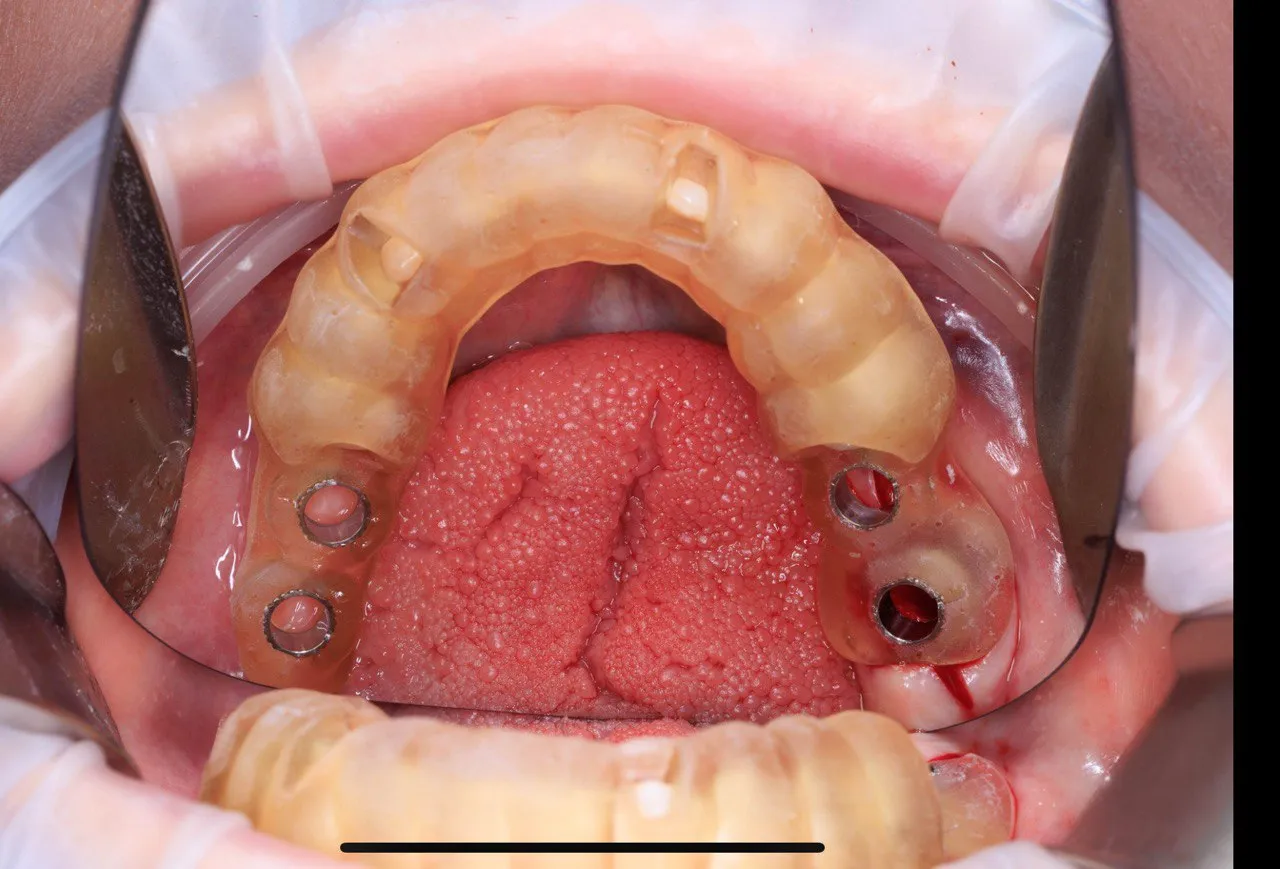

Dual Arch Rehabilitation — All-on-4 & All-on-6

Complete upper and lower jaw rehabilitation. All-on-4 concept for maxilla and All-on-6 for mandible with custom surgical guides.